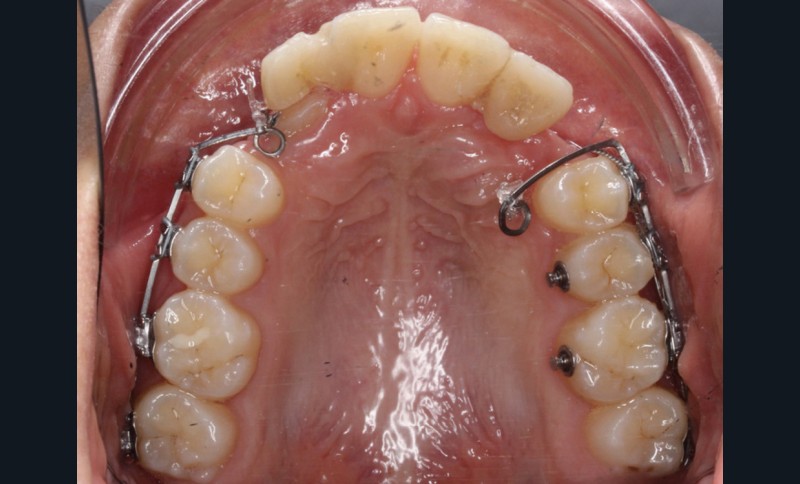

Un appareil multi-attaches .022 x .028 (prescription de Roth) est posé sur toute l’arcade mandibulaire et sur les secteurs postérieurs maxillaires (17 à 14 et 27 à 24) afin d’éviter au maximum la sollicitation de 11 et 21 et donc de limiter les résorptions radiculaires.

La désinclusion des canines a été réalisée dans un deuxième temps opératoire après trois semaines de cicatrisation muqueuse afin d’avoir une quantité de gencive attachée suffisante lors de la réalisation des lambeaux. Un lambeau déplacé apicalement a été réalisé pour désinclure la 13, avec une direction de traction distale sur une potence soudée sur le sectionnel activée après trois semaines de cicatrisation (fig. 3). Un lambeau muco-périosté repositionné a été réalisé pour désinclure la 23 qui a été immédiatement mise en charge par traction distale sur un bouton palatin collé sur 25. Un approfondissement vestibulaire mandibulaire antérieur a ensuite été réalisé.

La traction des canines incluses s’est faite sur des sectionnels postérieurs en TMA .017 x .025 de type Ballista (fig. 4a,b). Un décapuchonnage de la 23 a dû être réalisé pour lui permettre de transpercer la muqueuse palatine. Des cales occlusales ont été ajoutées pour assurer le passage de la canine de la situation palatine à vestibulaire. Un contrôle radiologique a permis de suivre la traction. Parallèlement, la fermeture des espaces mandibulaires s’est faite par perte d’ancrage postérieure et par redressement antérieur grâce à des chaînettes élastomériques.